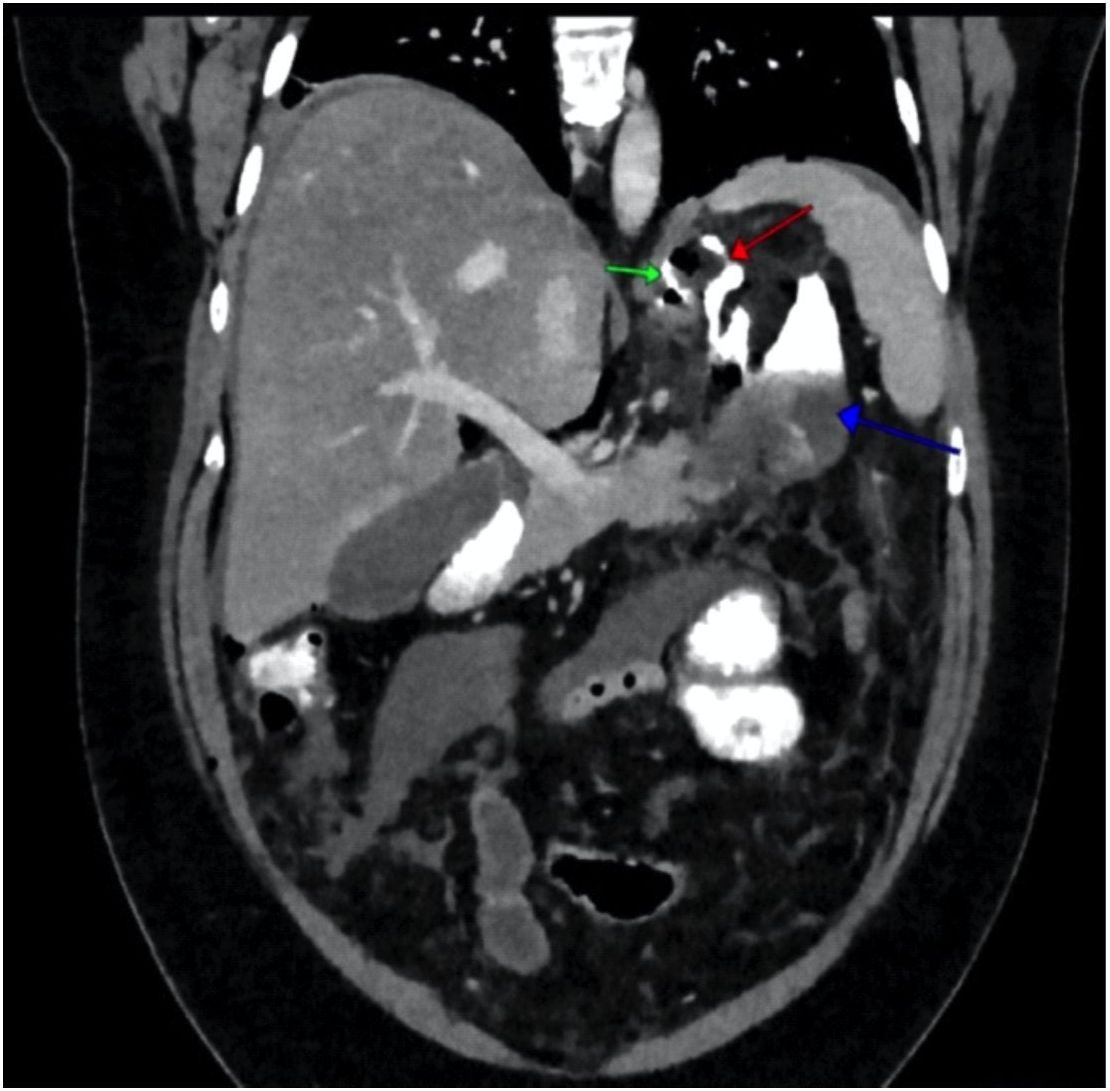

Однако на следующие сутки зафиксирован нейтрофильный лейкоцитоз: лейкоциты 19,41 · 109/л (референс: 4,5–11,0), нейтрофилы 18,8 · 109/л (референс: 1,56–6,13), лимфоциты 0,31 · 109/л (референс: 1,18–3,74), моноциты 0,3 · 109/л (референс: 0,4–1,1), и повышение уровня СРБ до 85 мг/мл (референс: 0–5), в связи с чем выполнена компьютерная томография (КТ) брюшной полости с пероральным и внутривенным контрастированием. В поддиафрагмальном пространстве слева вблизи кардиального жома обнаружено отграниченное скопление жидкости 7,5 × 6 × 11 см, со следами контрастного вещества, что свидетельствовало о несостоятельности скрепочного шва в области кардиального отдела культи желудка (рис. 2).

Рис. 2. Мультиспиральная компьютерная томография брюшной полости с внутривенным и пероральным контрастированием. Фронтальная MPR-реконструкция. Дефект в области скрепочного шва (зеленая стрелка) с контрастированием хода в левом поддиафрагмальном пространстве (красная стрелка) и затеком контрастной взвеси в отграниченное жидкостное скопление (синяя стрелка)